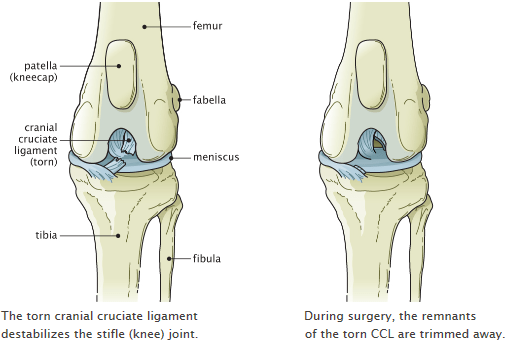

Pros And Cons Of Luxating Patella Surgery. The hospital will give you individualized recovery instructions. As the patella moves in and out of the groove it can wear holes in the cartilage of the patella itself and in the ridge that it rides over when it luxates. Leave a Comment Uncategorized. This causes pain and triggers a cascade of progressive osteoarthritis.

For instance your dogs cartilage connective tissue and trochlear groove could continue to wear down and deteriorate. However his enthusiasm and love for life overrides any pain or discomfort he feels a problem I know all to well from. Recovery From Luxating Patella Surgery. Most of these second surgeries are done because of knee pain. If your dog is not limping frequently and not having her quality of life compromised then a surgery is probably not necessary. As the puppies get bigger the structure can change enough to keep that kneecap in pace.

Reconstruction will release tight tissues and tighten loose tissues. The longer the patella. Risks of delaying luxating patella surgery. So second vote for surgery. Also the abnormal pull of the quadriceps causes internal rotation of the tibia relative to the femur that can stress other structures within the knee including the cranial cruciate ligament CCL.